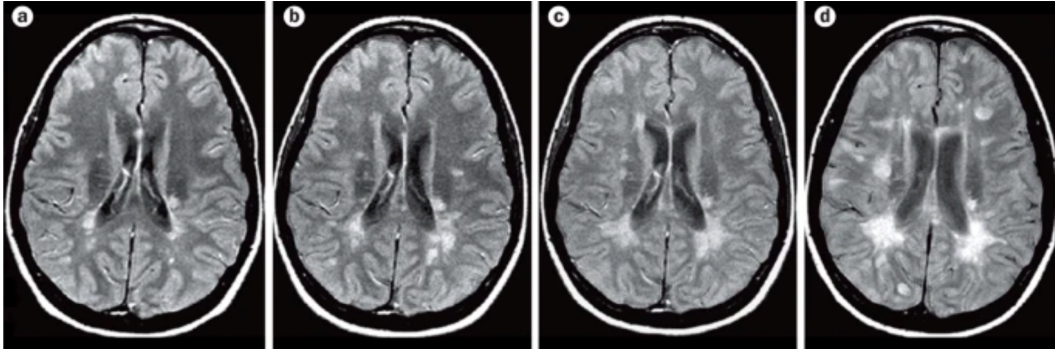

Um exame neurológico completo realizado por um Neurologista especialista ajuda a avaliar o estado neurológico do paciente, enquanto a confirmação diagnóstica pode ser feita através da realização de Ressonância Magnética de Crânio e Coluna (demonstrando lesões da doença) e da coleta de Líquor através de punção lombar (demonstrando, em muitos casos, a presença de bandas oligoclonais).